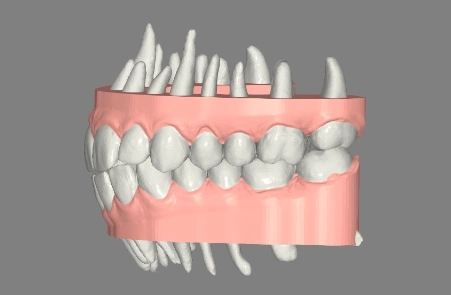

Wir nutzen DVT- oder 3D-Aufnahmen, um Ihren Kiefer präzise darzustellen und den idealen Platz für jeden Pin zu bestimmen.

Scan, DVT & Überlagerung

Wir analysieren Knochen, Nervenbahnen und Wurzeln, um die sichersten Pin-Zonen festzulegen.

Digitale Pin-Planung

Wir nutzen Software, um die präzise Platzierung der Pins zu planen – für eine optimale Kraftrichtung, abgestimmt auf Ihre Anatomie und Bewegungsziele.